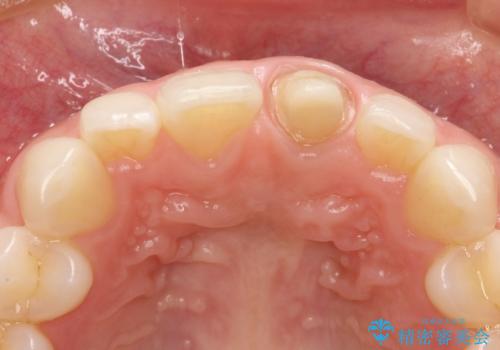

- 以前装着された前歯のかぶせ物の色を変えたいとのことで来院されました。

土台からの再治療を行い、オールセラミッククラウンを装着する治療計画としました。